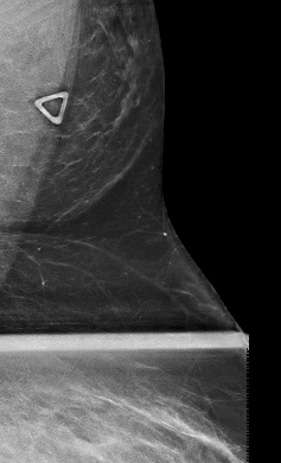

Ectopic Axillary Breast Tissue | Image | Radiopaedia.org

Ectopic axillary breast tissue | Image | Radiopaedia.org radiopaedia.orgUnilateral Accessory Axillary Breast Tissue In A Male Patient | Eurorad

Accessory breast tissue | Image | Radiopaedia.org radiopaedia.orgFibroadenoma Of The Ectopic Axillary Breast Tissue: Sonographic Appearances

Fibroadenoma of the Ectopic Axillary Breast Tissue: Sonographic Appearances file.scirp.orgfibroadenoma tissue ectopic axillary